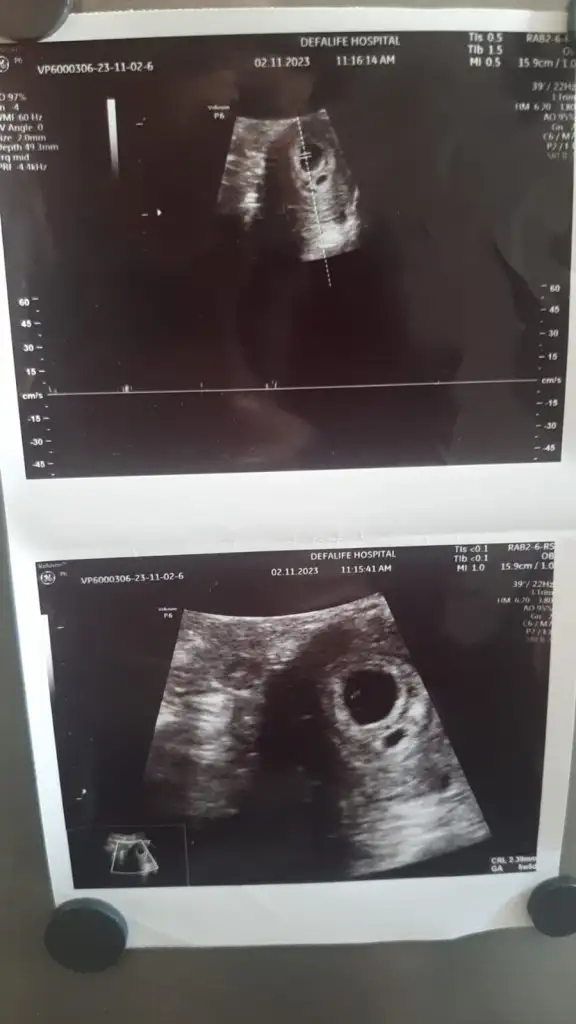

Merhaba lar hanımlar ilk 2 resim 11 haftalikken diğer resimlerde 15 haftalikken banada tahminde bulunurmusunuz